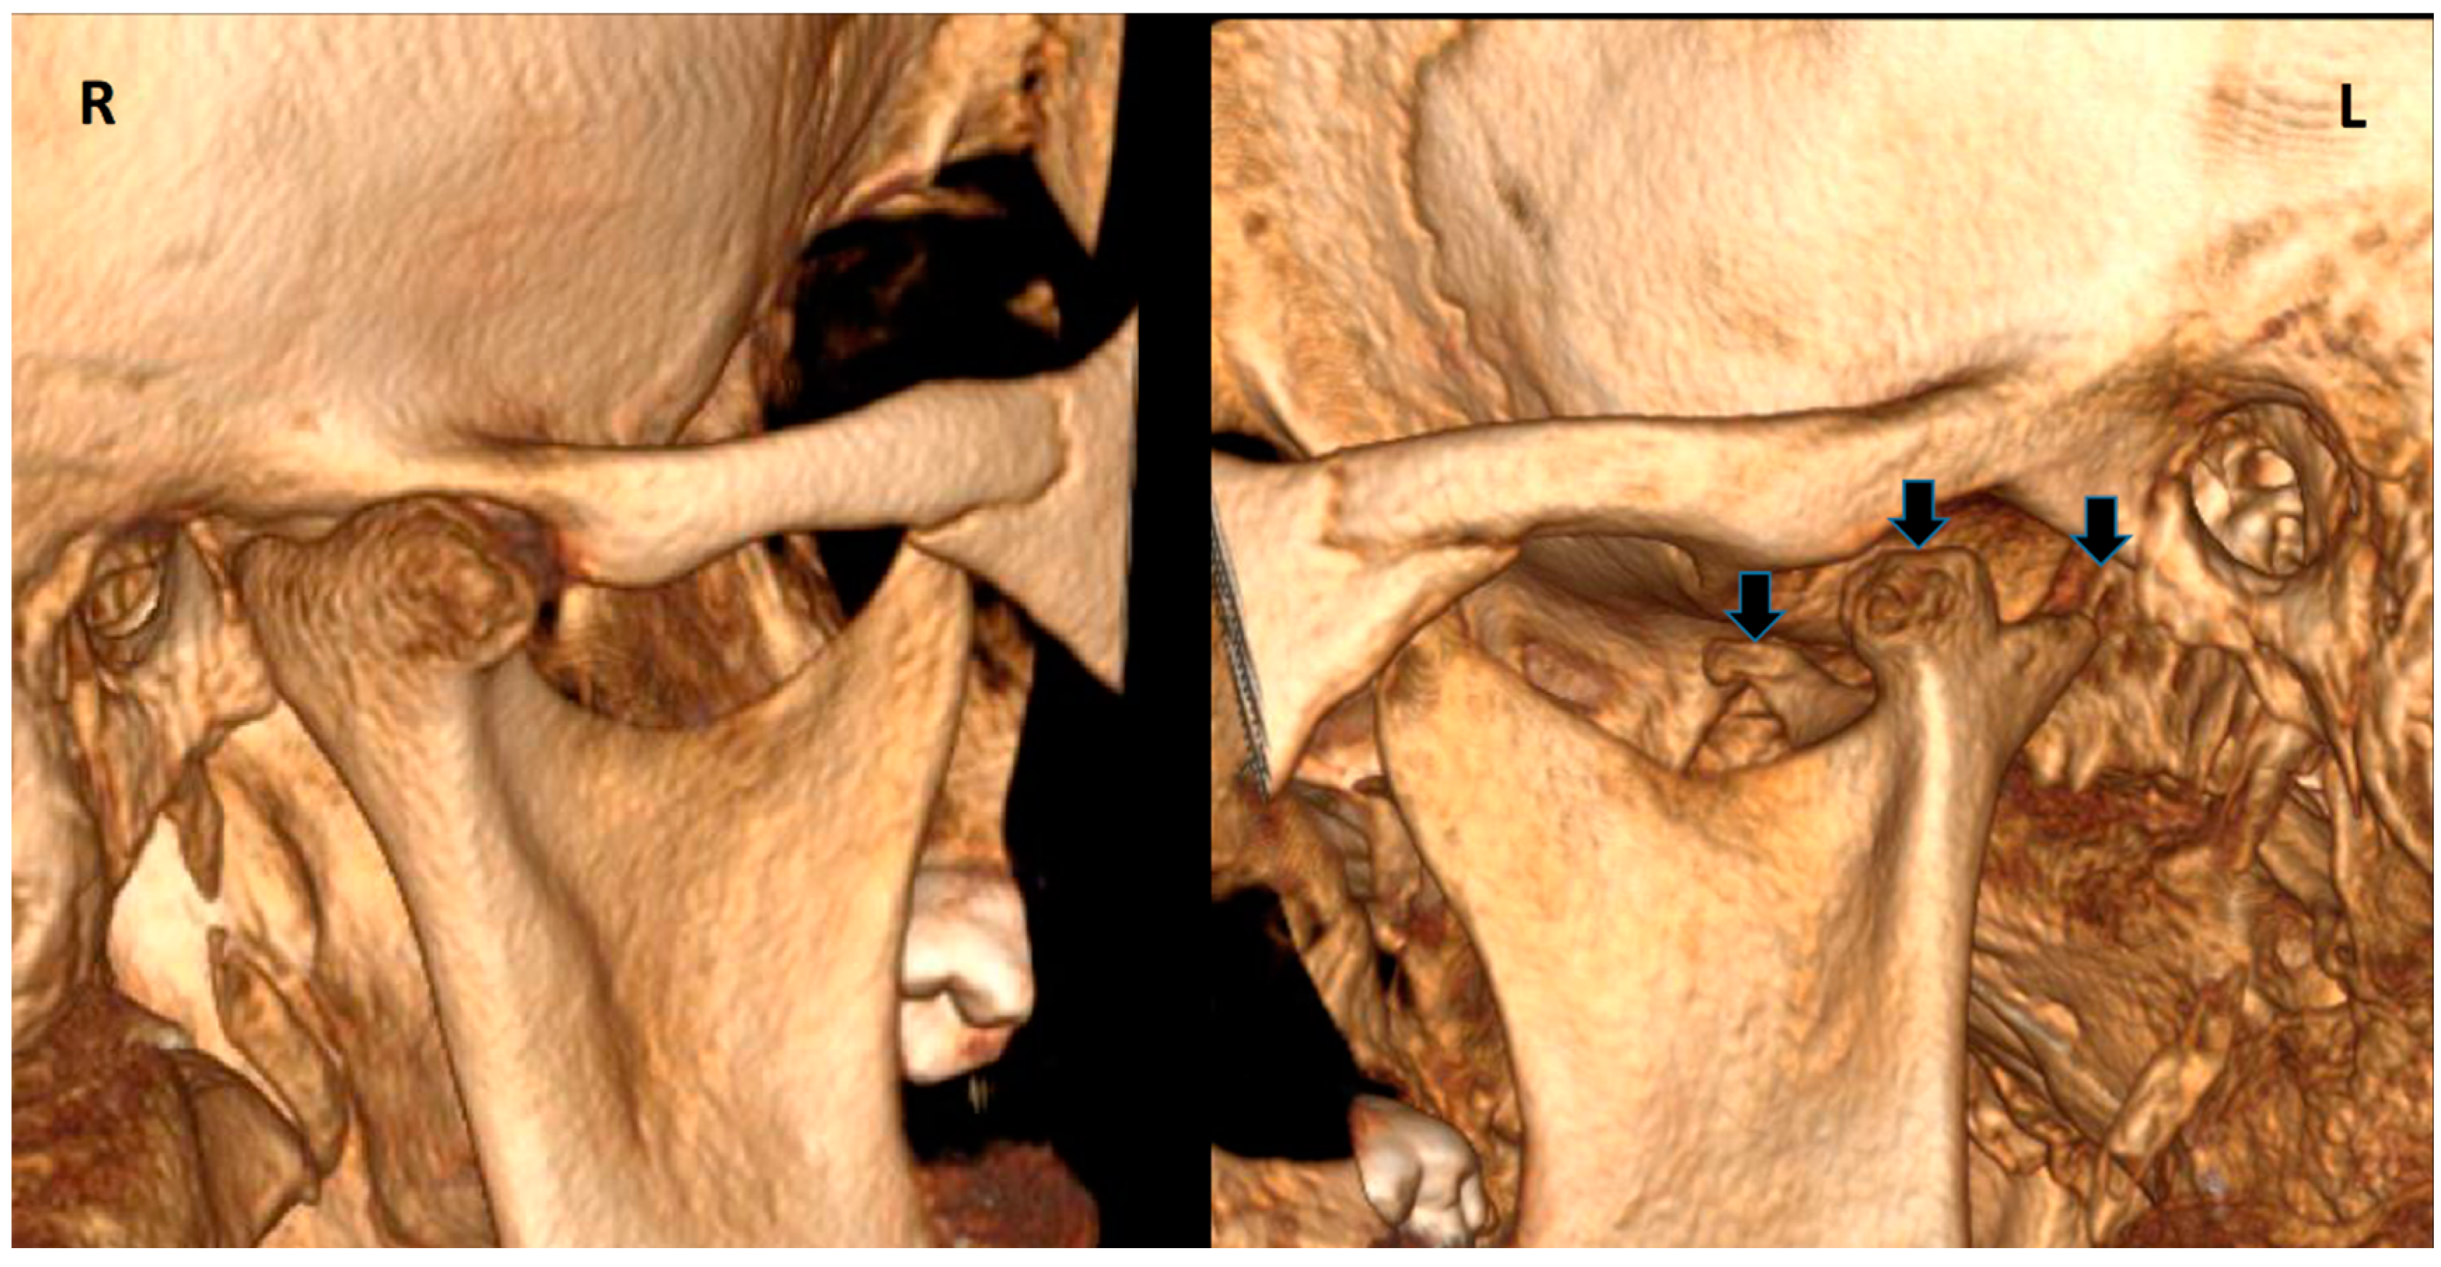

2. Case Report